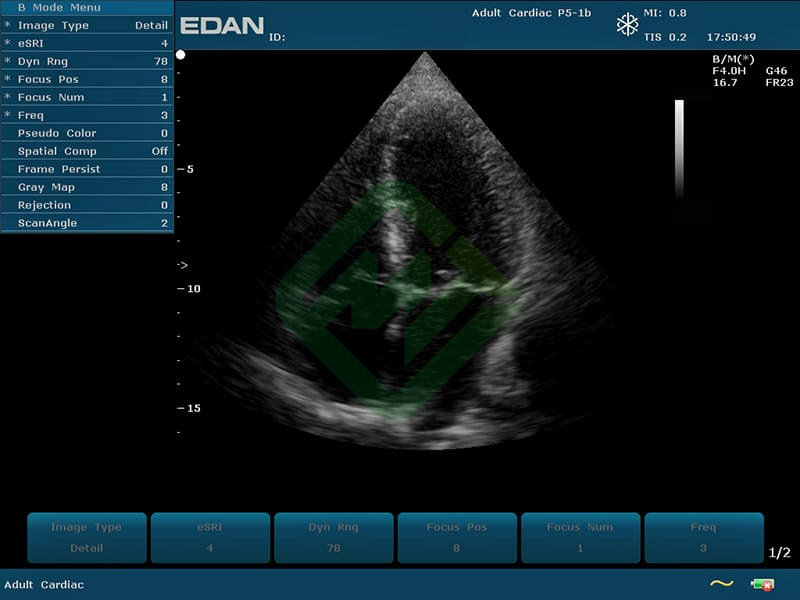

- Предназначен для гинекологических, акушерских, педиатрических, урологических, трансвагинальных и кардиологических исследований, а также исследований брюшной полости, поверхностных органов, периферических сосудов и опорно-двигательного аппарата

— фазированным P5-1b: частотный диапазон датчика 1,8–4,3 МГц, угол обзора 90°, глубина сканирования 320 мм, количество элементов 64 - Также для U50 подходят датчики (приобретаются отдельно):

- Датчик фазированный ультразвуковой P5-1b — 1 шт.